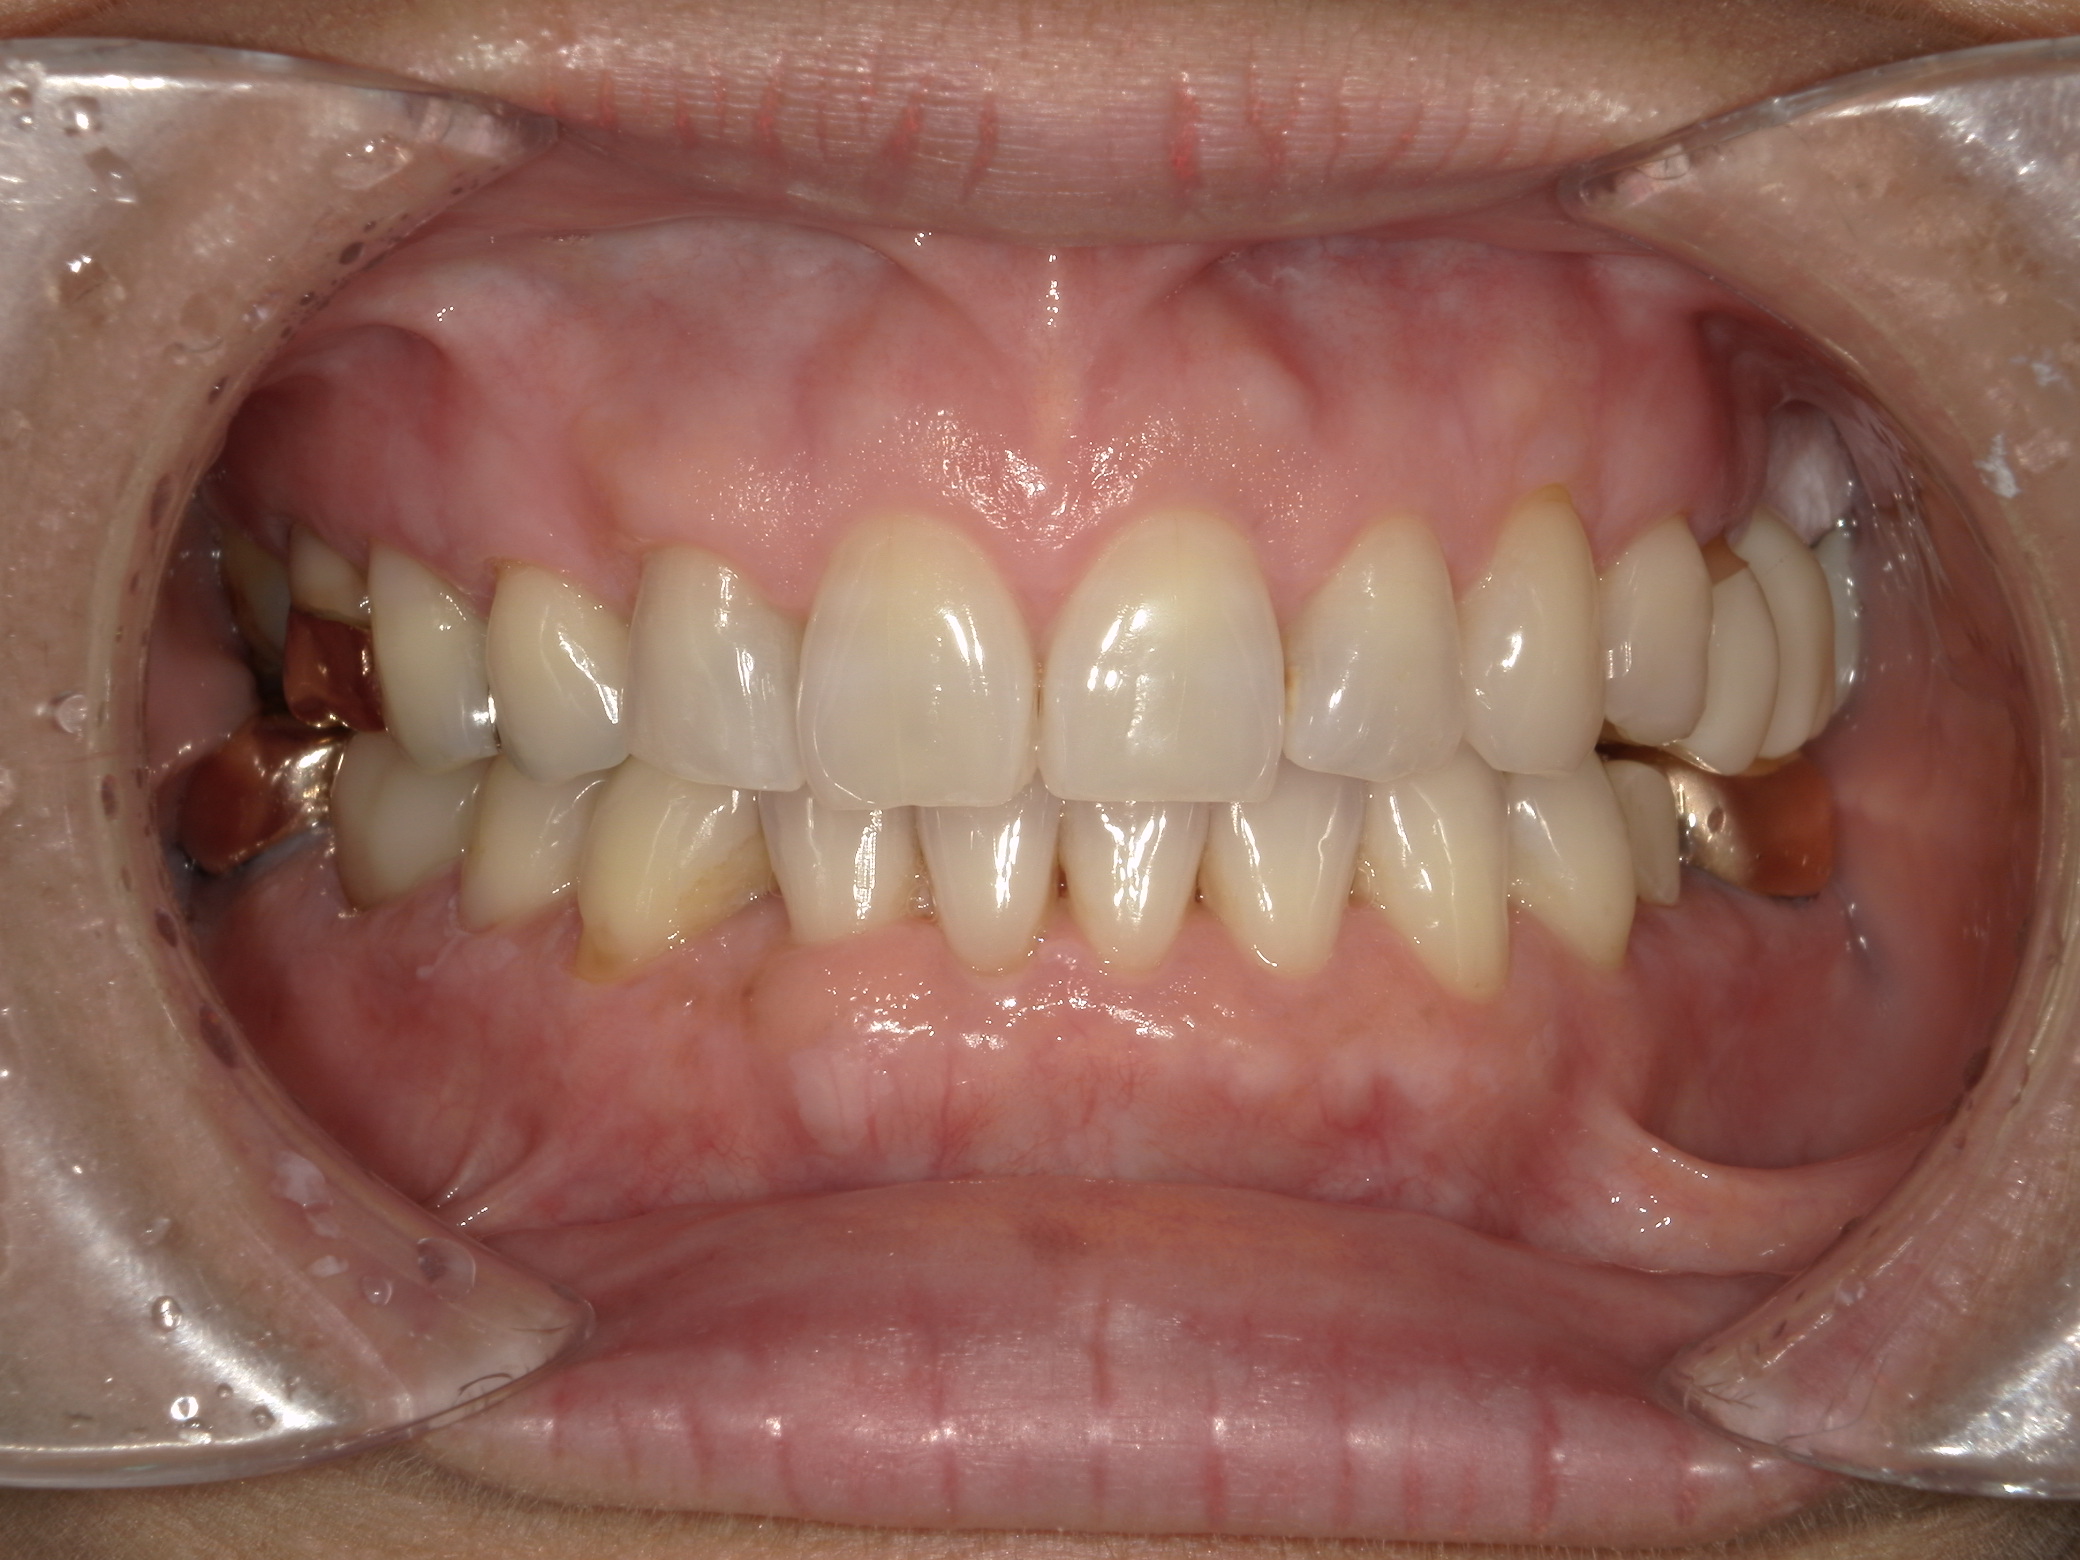

治療前

治療後